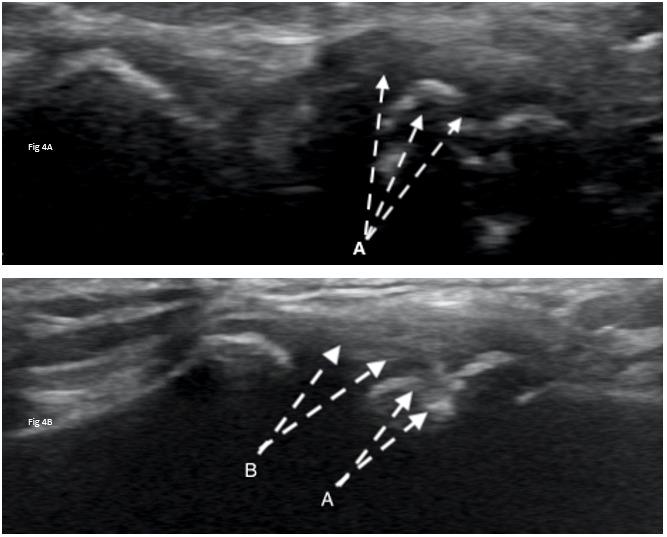

Interest is gaining in US’s ability to view muscles both statically and dynamically 34–40 Dynamic US protocols have been published by an international group of experts to help clinicians evaluate structures while recording video during real-time patient examination to improve their understanding of their diagnosis.41–44 Dynamic ultrasound allows for real-time visualization of structures as they move in relation to other structures. For example, the movement of adjacent fascial layers can be evaluated during active muscle contraction to assess fascial mobility. Muscle architecture can be examined under contraction or relaxation for deficits.

Clinicians must have a keen knowledge of regional anatomy and palpation skills to ensure proper position of the transducer over the target tissue. The transducer should be held perpendicular to the skin with the indicator directed proximal and/or lateral; this standard positioning orients the examiner with the image. Most commonly, MSUS views can be viewed in either a short axis (transverse)

or long axis (longitudinal). The short axis (SAX) is performed through the transverse plane of the intended tissue, while the long axis (LAX) is performed along the longitudinal length of the tissue (See Figure 2). When possible, it is best to visualize both to get an accurate representation of the entire tissue.